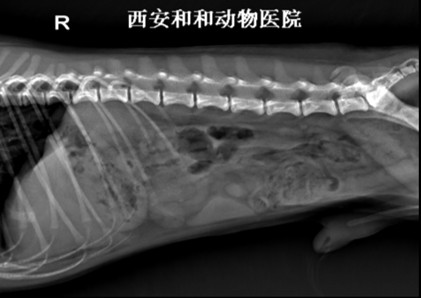

腹腔侧位片示例 |

资源描述:将后肢向后牵拉使之与脊柱约成120°角。X射线束中心对准腹中部(最后肋骨后缘),照射范围包括:前界含膈,后界达髋关节,上界含脊柱,下界达腹底壁。

文件来源:西安京和动物医院有限公司